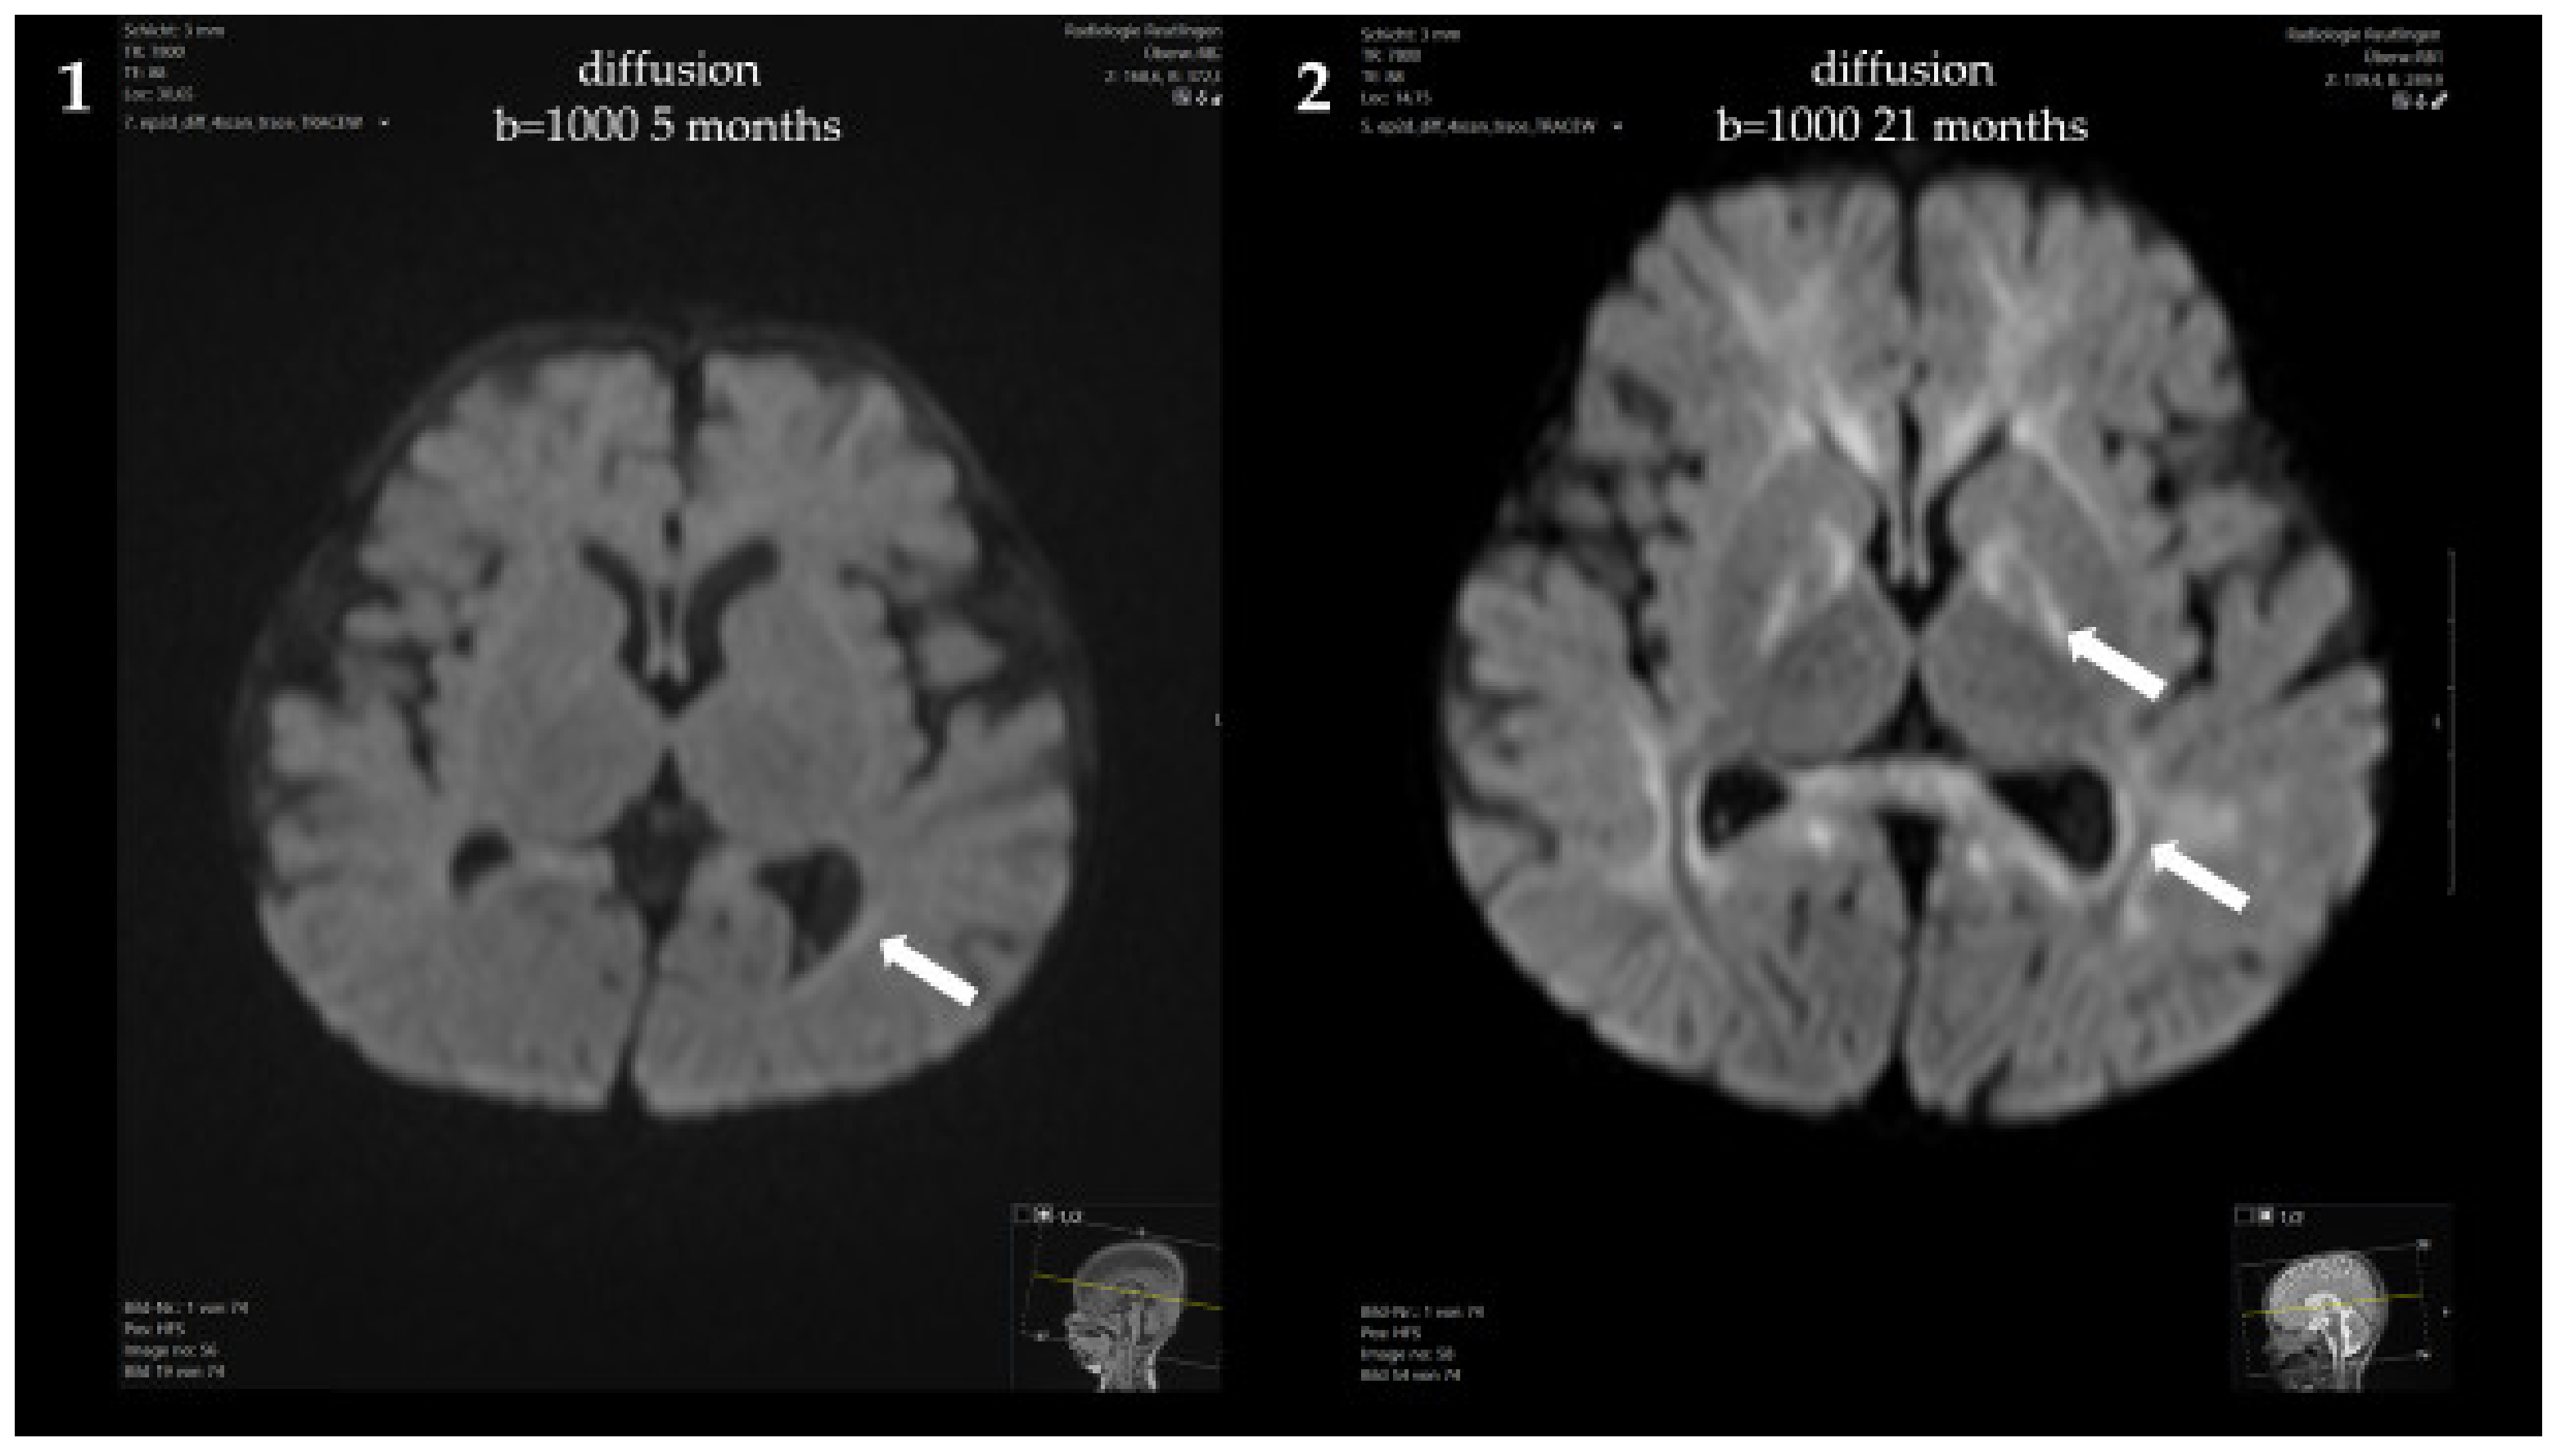

At 5 months, a brain MRI revealed mildly delayed myelination, dilated inner and outer cerebrospinal fluid spaces and mild periventricular diffusion interference (Figure 2). Clinically, the patient showed mild, predominantly motor, developmental delay (no hand support possible in prone position; no age-appropriate head posture; no turning of the child in prone and/or supine position) and mild muscular hypotonia. From 5 to 8 months of age, weight stagnation—likely due to decreased caloric intake—was observed. Dietary adaptation with an age-adequate calorie intake resulted in catch-up growth and normal weight at 14 months of age. Psychomotor development and muscle tone normalized.

Figure 2.

Brain MRI of the patient: (1,3) At 5 months, showing mildly delayed myelination, dilated inner and outer cerebrospinal fluid spaces and mild periventricular diffusion interference; (2,4) At 21 months, showing progressive diffusion impairment.

Psychomotor development at the age of 21 months was age-appropriate, and the patient showed normal growth under the Met-restricted diet (25 mg Met/kg/day). Met concentrations remained below 600 μmol/L. The concentration of AdoMet was normal (95.9 nmol/L, reference range 71–118 nmol/L). Despite the lack of neurological symptoms, a brain MRI at 21 months showed progressive diffusion impairment, but no structural abnormalities.